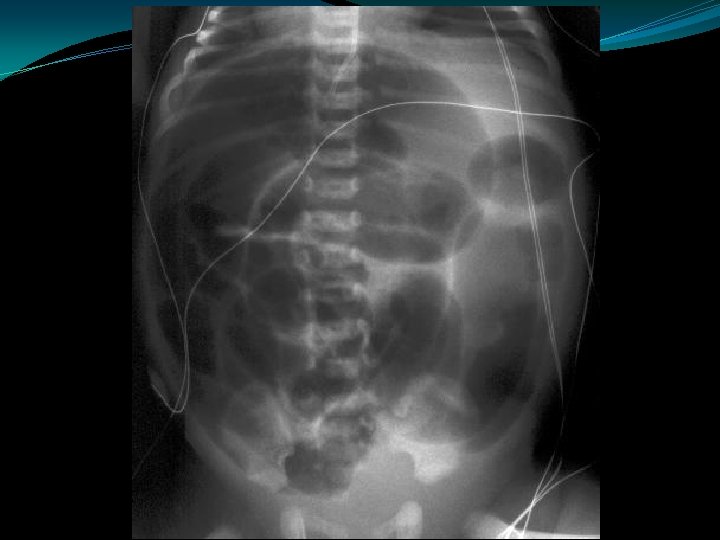

Meconium Ileus �Usually a manifestation of cystic fibrosis � 20% of infants with CF present with mec ileus �Obstruction of proximal ileum by thick, sticky round meconium pellets �Absence of air fluid levels �“soap bubbles” �Complications: �perforation, peritonitis, pseudocyst, ileal atresia/stenosis

Meconium Ileus �Contrast enema: �Small colon �Filled with pellet-like meconium when contrast extends to IC valve �Contrast can wash out the obstructing plugs and meconium plugs �The diagnosis of CF should be ruled-out